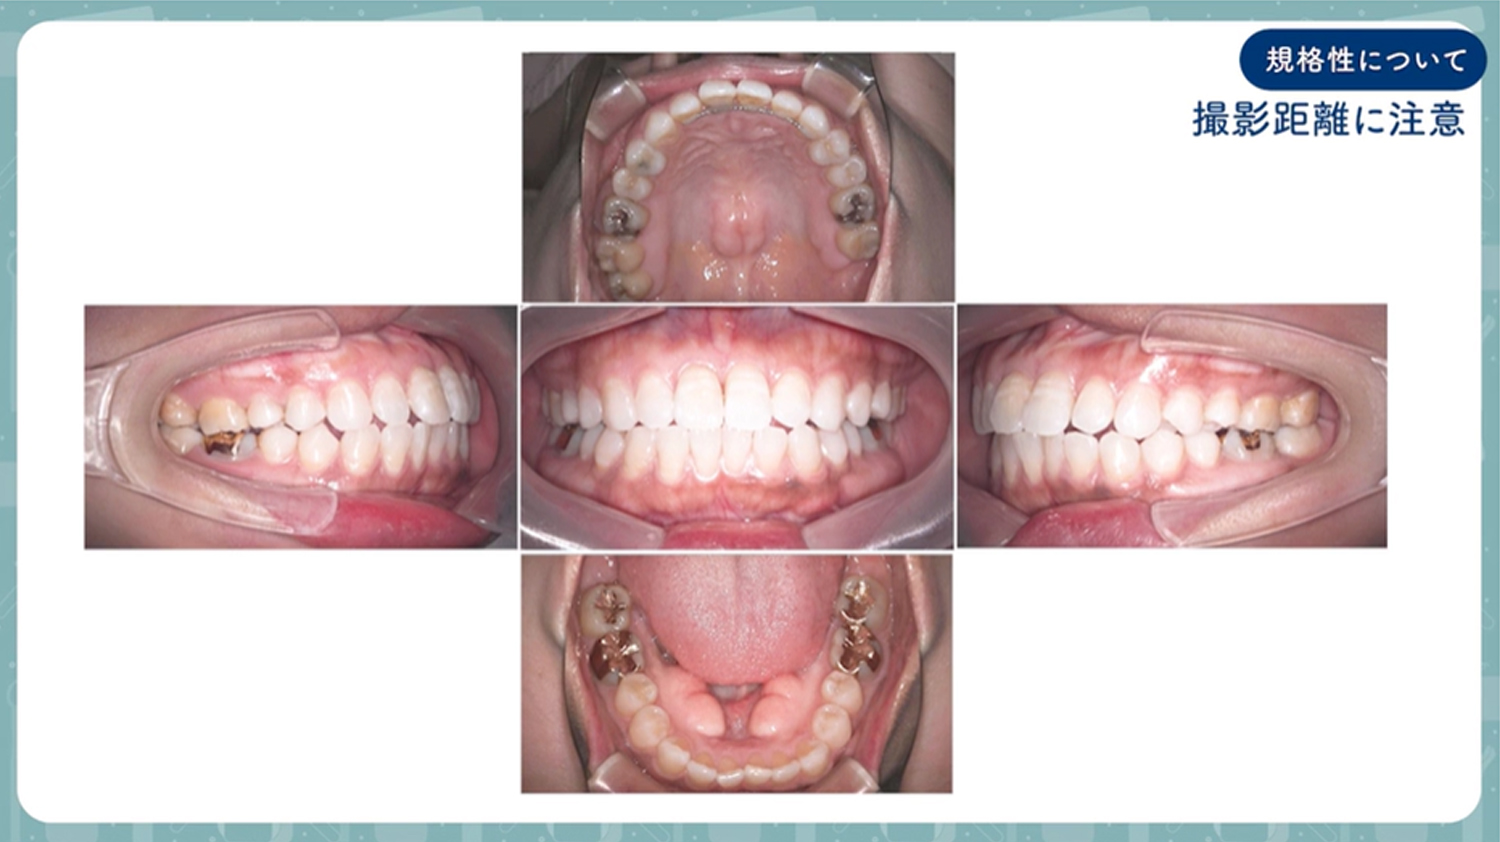

口腔内写真5枚法撮影手順

▶マニュアル動画はこちら